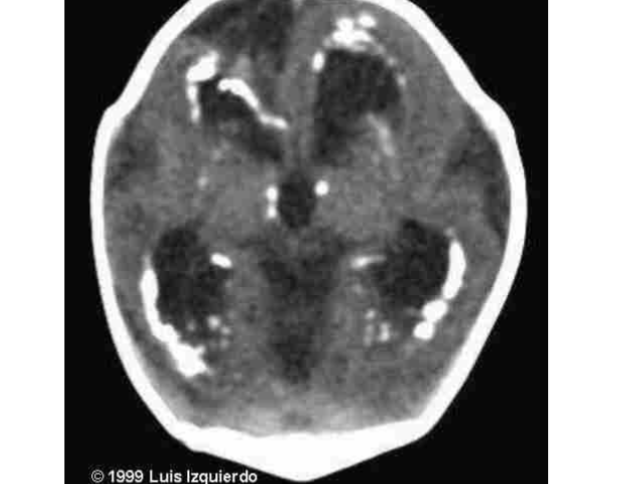

- ,There is symmetrical, bilateral, hyper-dense (whitish), rounded lesions - (1 :approximately 1.5 Ă 1.5 cm in diameter located in the basal ganglion regions

- .The diagnosis is Intra-cranial calcification - (2

- The cause is high dose of Vitamin D (One Alpha Calcidol ) which was - (3 -used to control hypocalcemia. The hypocalcemia is secondary hypo .parathyroidism which is a part of Middle East Syndrome .(Sanjad Saqqati Syndrome)

Newborn with jaundice, microcephaly, IUGR and hearing loss, the mother is rubella immune Purple skin lesion and petechiae with hepatosplenomegaly

what is the investigation ? Brain CT Diagnosis ? Toxoplasmosis